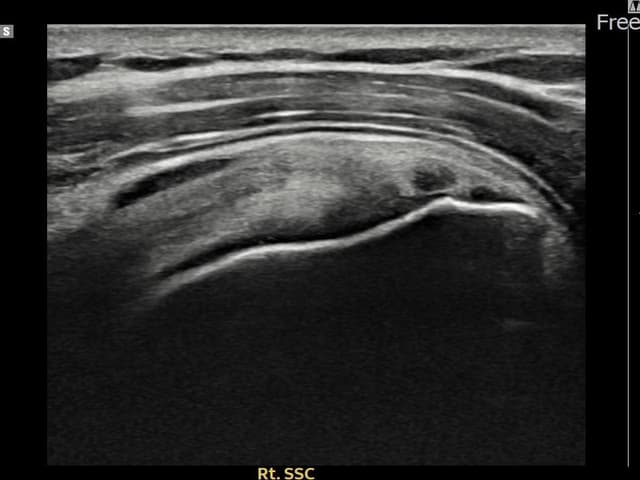

[経過期間: 24.03.04~24.05.10]

[縫縮術] 超音波検査にて右 견갑하근건 関節面側部分断裂(7mm × 3mm (腱厚の約28%欠損))を確認。縫縮術施行後、腱の連続性が回復し、日常生活に復帰されました。